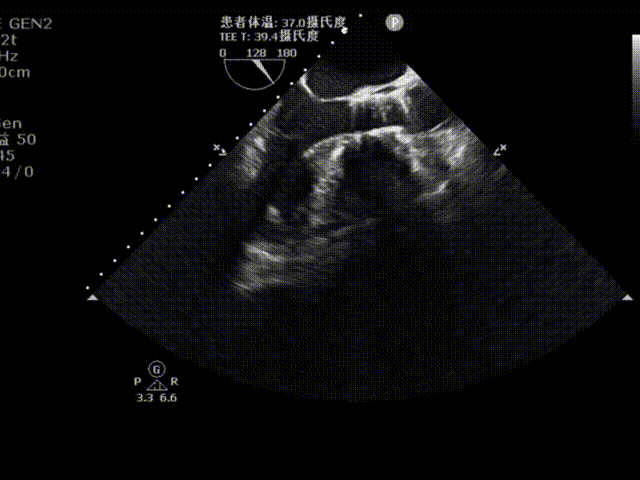

术后超声评估

植入后超声多切面评估,瓣膜位置理想,血流动力学改善显著。